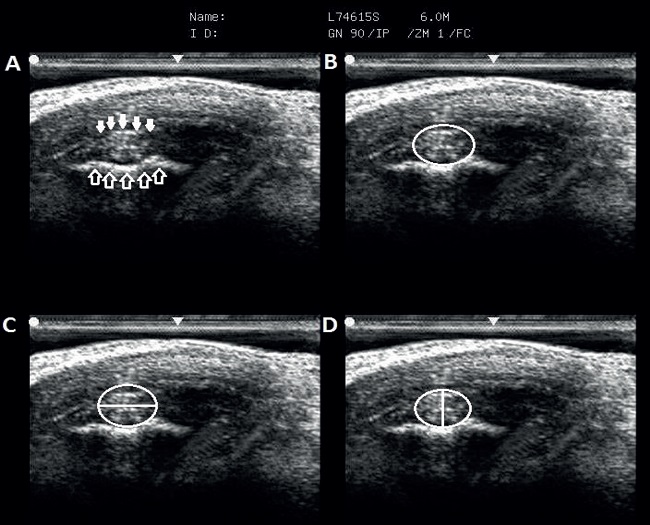

The ultrasonographic technique used in this study was recommended by Denoix et al. (2011), with the ultrasonographic cut-off in position A, in which CL-DIPJ is observed in the distal concavity of the middle phalanx. We measured the four CL-DIPJ of the thoracic limbs of each animal. For this, after animal preparation and probe positioning, three images of each studied ligament were captured. Measurements were performed in each of the images by means of the ultrasound equipment, which also allowed obtaining the values of CL-DIPJ area. With the three measurement values, the average of each variable was calculated. The sites for performing the measurements followed the recommendations of Contreras (2009) and the studied variables were named as the dorsopalmar diameter (DPD), latero-medial diameter (LMD), and cross-sectional area (CSA) of ligaments, which are shown in Figure 1.

The evaluator had a greater difficulty in obtaining images of the medial collateral ligaments (MCL), which was also reported by Whitcomb (2009) and Ribeiro (2016). In addition, although all the animals have presented hooves with similar characteristics, we observed slight variations in CL-DIPJ shapes, with some ligaments being flatter or more rounded and varying between individuals and between the lateral collateral ligaments (LCL) and MCL of the same individual. Denoix et al. (2011) and Ribeiro (2016) also described similar results. This characteristic did not cause a great complication to carry out the measurements, but it reinforces the fact that individuals have variations between each other and that an individual evaluation must be carried out carefully, respecting the characteristics of each animal.

In both thoracic limbs, the probe was positioned dorsolaterally and dorsomedially on the coronary band, as described by Turner and Sage (2002) and Evrard et al. (2012). This structure served as a window and allowed finding the concavity of the distal edge of the middle phalanx and using it as a reference point in the chosen position, as described by Denoix et al. (2011) and Turner and Sage (2002). Although CL-DIPJ has particular characteristics regarding their echogenicity during the ultrasonographic evaluation due to the variation in the direction of its ligament fibers along the length (DENOIX et al., 2011; EVRARD et al., 2012), the positioning allowed visualizing the ligament with echogenic characteristics without major difficulties. Moreover, in cases where an anisotropy was observed in position A, a slight adjustment in the probe angulation by the evaluator was sufficient to undo this effect.

The use of a linear probe at a frequency of 7.5 MHz is indicated for CL-DIPJ evaluation, especially to observe changes in echogenicity (DYSON et al., 2004; DENOIX et al., 2011). However, using a frequency of 6 MHz, although the loss of image quality to evaluate fiber echogenicity, we observed a better delimitation of this structure, avoiding a possible erroneous evaluation of CL-DIPJ size.